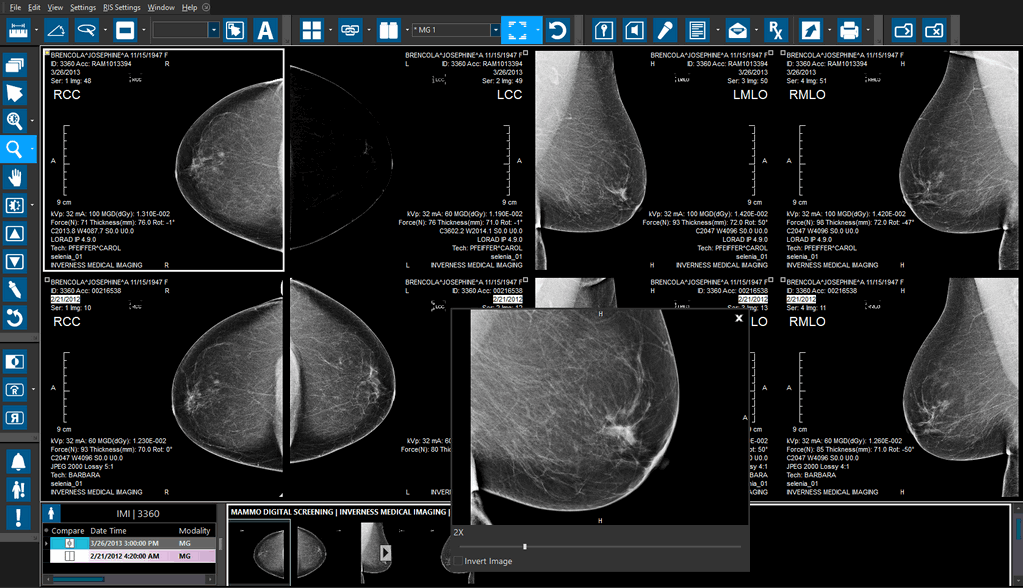

In PowerReader, open an MG study. In this example, the image is not fully zoomed in the viewport. Sometimes, MG studies received from other stations have this problem.

Once the protocol is refreshed, the study will display a larger scope of the viewport. This enlargement allows the user to examine the study in much more detail.